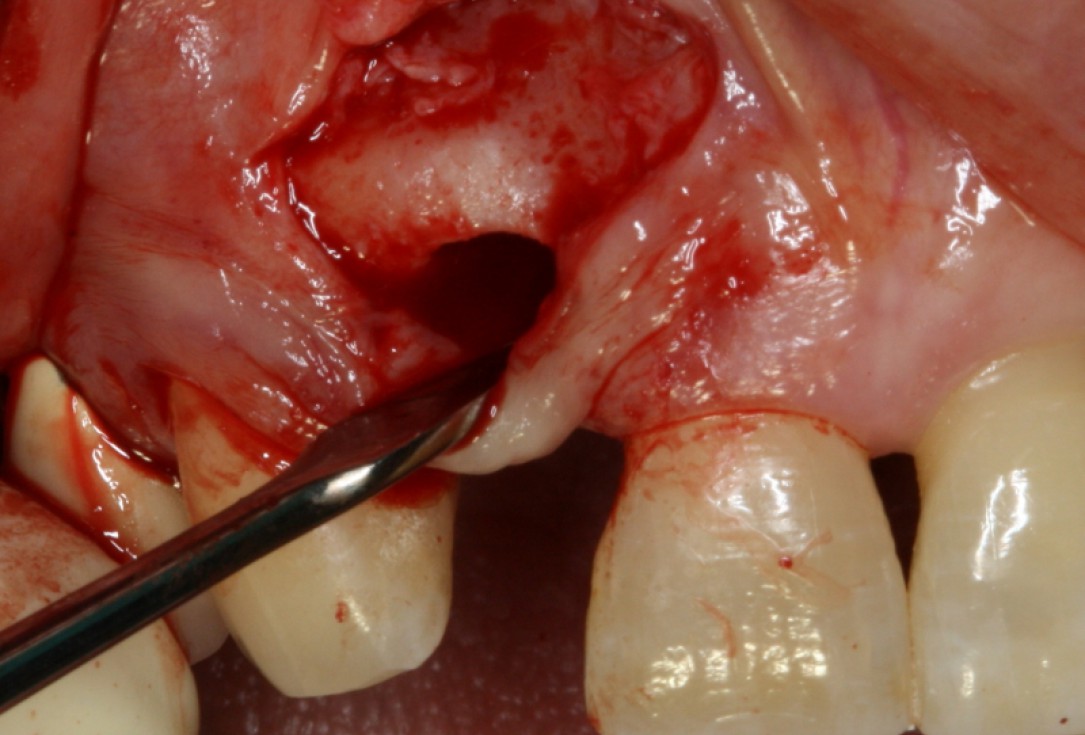

08/20 - Surgical presentation of the alveolar ridgeGBR with maxresorb® & Jason® membrane - Prof. Dr. Dr. D. Rothamel

-